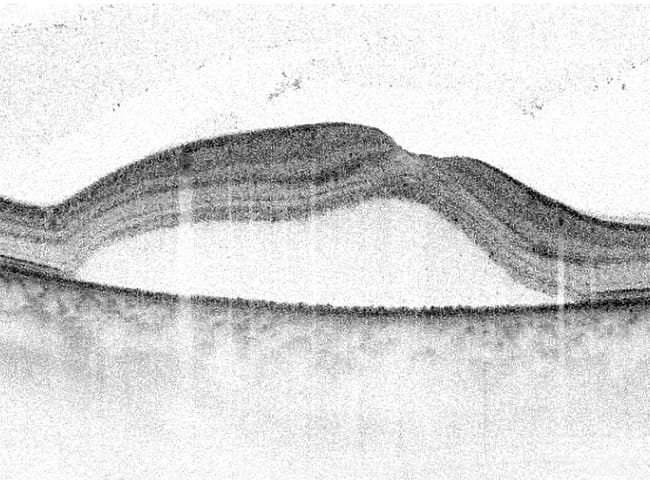

La corioretinopatia sierosa centrale è una malattia della retina caratterizzata dall’accumulo di fluido al di sotto della macula. La patogenesi tutt’ora non è del tutto chiara, ma diversi studi hanno dimostrato come alla base del meccanismo che porta all’accumulo di liquido ci sia proprio un aumento della permeabilità della coroide che a seguito di piccole rotture della barriera formata dallo strato dell’epitelio pigmentato retinico, si accumula al di sotto della macula, la solleva e forma una bolla con conseguente riduzione della visione.

Clinicamente, all’esame del fondo oculare, si osserva un tipico sollevamento della retina a forma di bolla, a contenuto sieroso, nella regione maculare. Non è raro ritrovare, nelle forme recidivanti, un’alterazione cronica dell’epitelio pigmentato retinico sotto forma di zone di atrofia o di rimaneggiamento pigmentario. La formazione di queste lesioni è favorita dal sollevamento della retina che riduce l’apporto nutrizionale dalla sottostante coroide, determina un danno permanente al tessuto retinico. In alcuni casi come in gravidanza o quando si assumono corticosteroidi il fluido può essere fibrinoso, segno di marcata permeabilità della coroide.

- Tomografia a coerenza ottica (OCT): tecnica diagnostica non invasiva, utile per valutare all’inizio il sollevamento retinico maculare e monitorare le variazioni nei controlli.Nelle forme croniche, inoltre, si possono osservare le alterazioni strutturali retiniche alla base del mancato recupero funzionale;